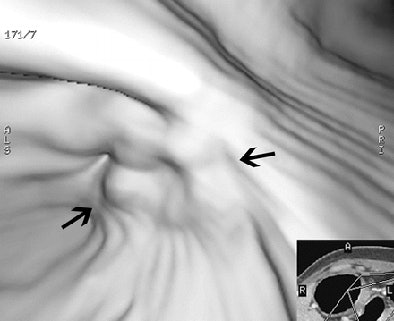

| Early gastric cancer in a 33-year-old woman. There is no identifiable gastric wall thickening on either the transverse CT scan (a, above) or the coronal MPR image (b, below). Virtual endoscopic image (c, bottom) shows a shallow depressed lesion with surrounding mucosal nodularity (arrows) in the angle of the stomach, suggesting early gastric cancer (T1). At histopathologic analysis, this lesion was diagnosed as type IIb + IIc early gastric cancer (pT1). Images used with permission of the Radiological Society of North America (Radiology 2005 Sep;236(3):879-85). |